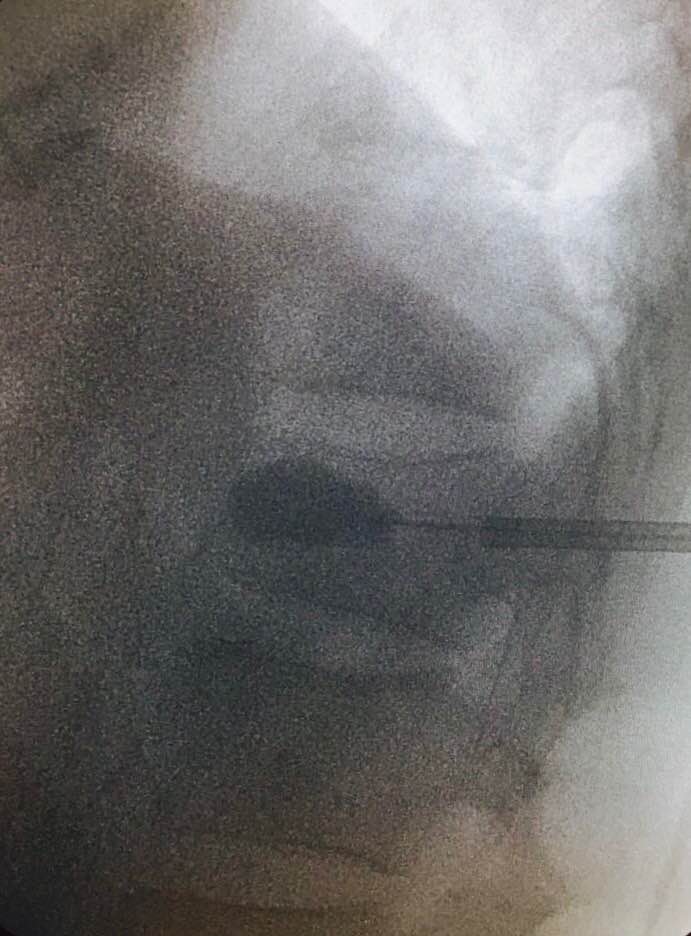

嚴重的工業意外受傷,T12胸脊椎不穩定的3段(前、中、後柱列)壓迫性脊柱椎體骨折

1. 即使您的胸部及胸脊椎柱被8英尺高和200磅重的巨大雪櫃嚴重壓碎, 您仍然生存, 您的中樞脊髓神經但沒有受到傷害.

2. 即使公立醫院忽畧了你不穩定的前、中、後3柱列的T12胸脊椎骨折,並在3天後容許你出院送回家, 你到私家醫院再進行第二次詳細檢查!

3. 幸運的是,入院前及兩天來你未有因為不穩定的脊柱椎體骨折碎片的移位而導致你脊髓中樞神經到不可逆轉和永久性的損傷致雙腿癱瘓及大小便失禁. 今天所有穩定你碎裂脊椎的手術都做完了.